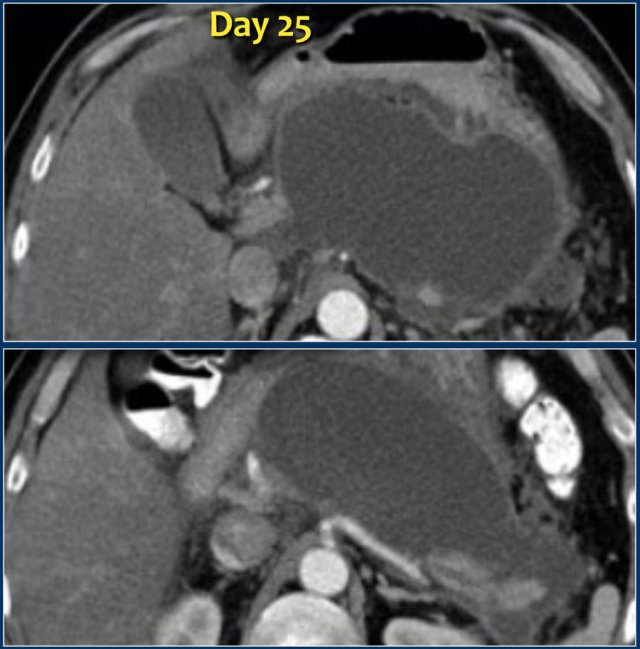

Here we see a homogeneous pancreatic and peripancreatic collection, well demarcated with an enhancing wall, on day 25 of an episode of acute necrotizing pancreatitis.

This patient had fever and multiple organ failure.

Therefore, this collection was suspected to be infected WON and not a pseudocyst.

At surgery, the collection contained much necrotic debris, which was not depicted on CT.

These cases illustrate that at times CT cannot reliably differentiate between collections that consist of fluid only and those that contain fluid and solid necrotic debris with or without infection.